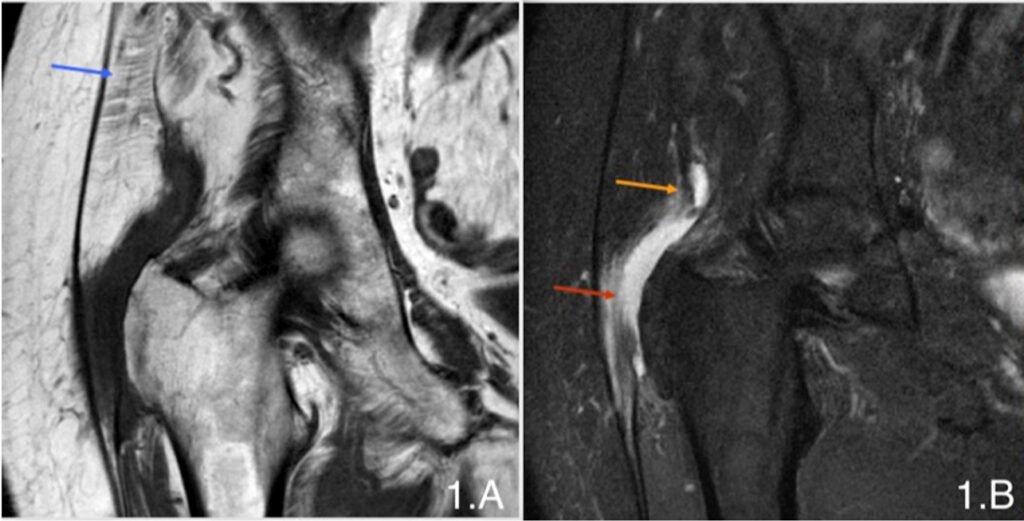

• Pre-Surgical Assessment: Dr Scott Tulloch will evaluate your condition through a physical examination and imaging tests, such as an MRI or ultrasound, to assess the extent of tendon damage.